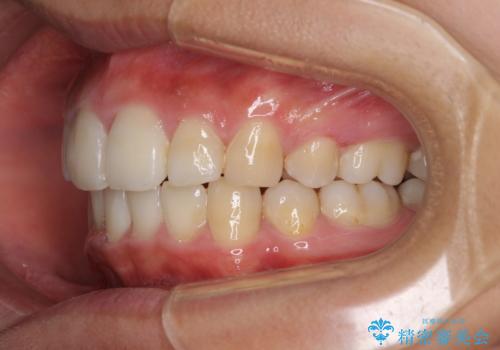

- 上下の出っ歯を気にして来院された患者様です。

口元を積極的に引っ込めるために、上下左右の第一小臼歯を4本抜歯することとしました。

しっかりと通院するようになってからは順調に治療が進み、横顔の印象が変わるほどスッキリとした口元となりました。